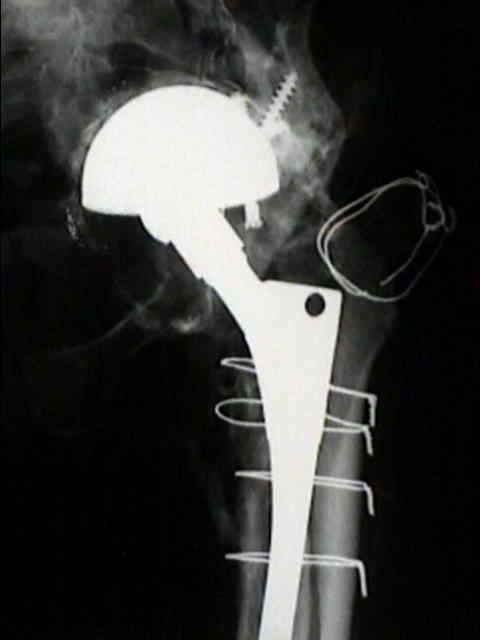

Loosening of Cemented Acetablar Components

(cemented acetabular component)

- radiolucency upto 2 mm wide with or without a surrounding fine line of density may develop in one or more of the the three zones about cement mass in the pelvis;

- as in the femur, radiolucency is produced by the dense fibrous membrane and in some areas, fibrocartilage that forms about the surface of the cement and the surrounding shell of reactive bone;

- loosening commonly occurs at the stem cement interface, but it rarely occurs at the cup cement interface;

definite loosening

- migration of component of more than 5 mm;

- crack in cement mantle;

probable loosening

- continuous radiolucent line > 1-2 mm wide at the bone cement interface;

- as pointed out by Hodgkins et al 1988, the finding of a continuous radiolucent line about the acetabular component indicates loosening in 94% of patients;

possible loosening

- non circumferential radiolucency which extends at least 50% around the bone cement interface;

implications of loosening

- even w/ radiographic loosening, only 10% of these hips will require revision;